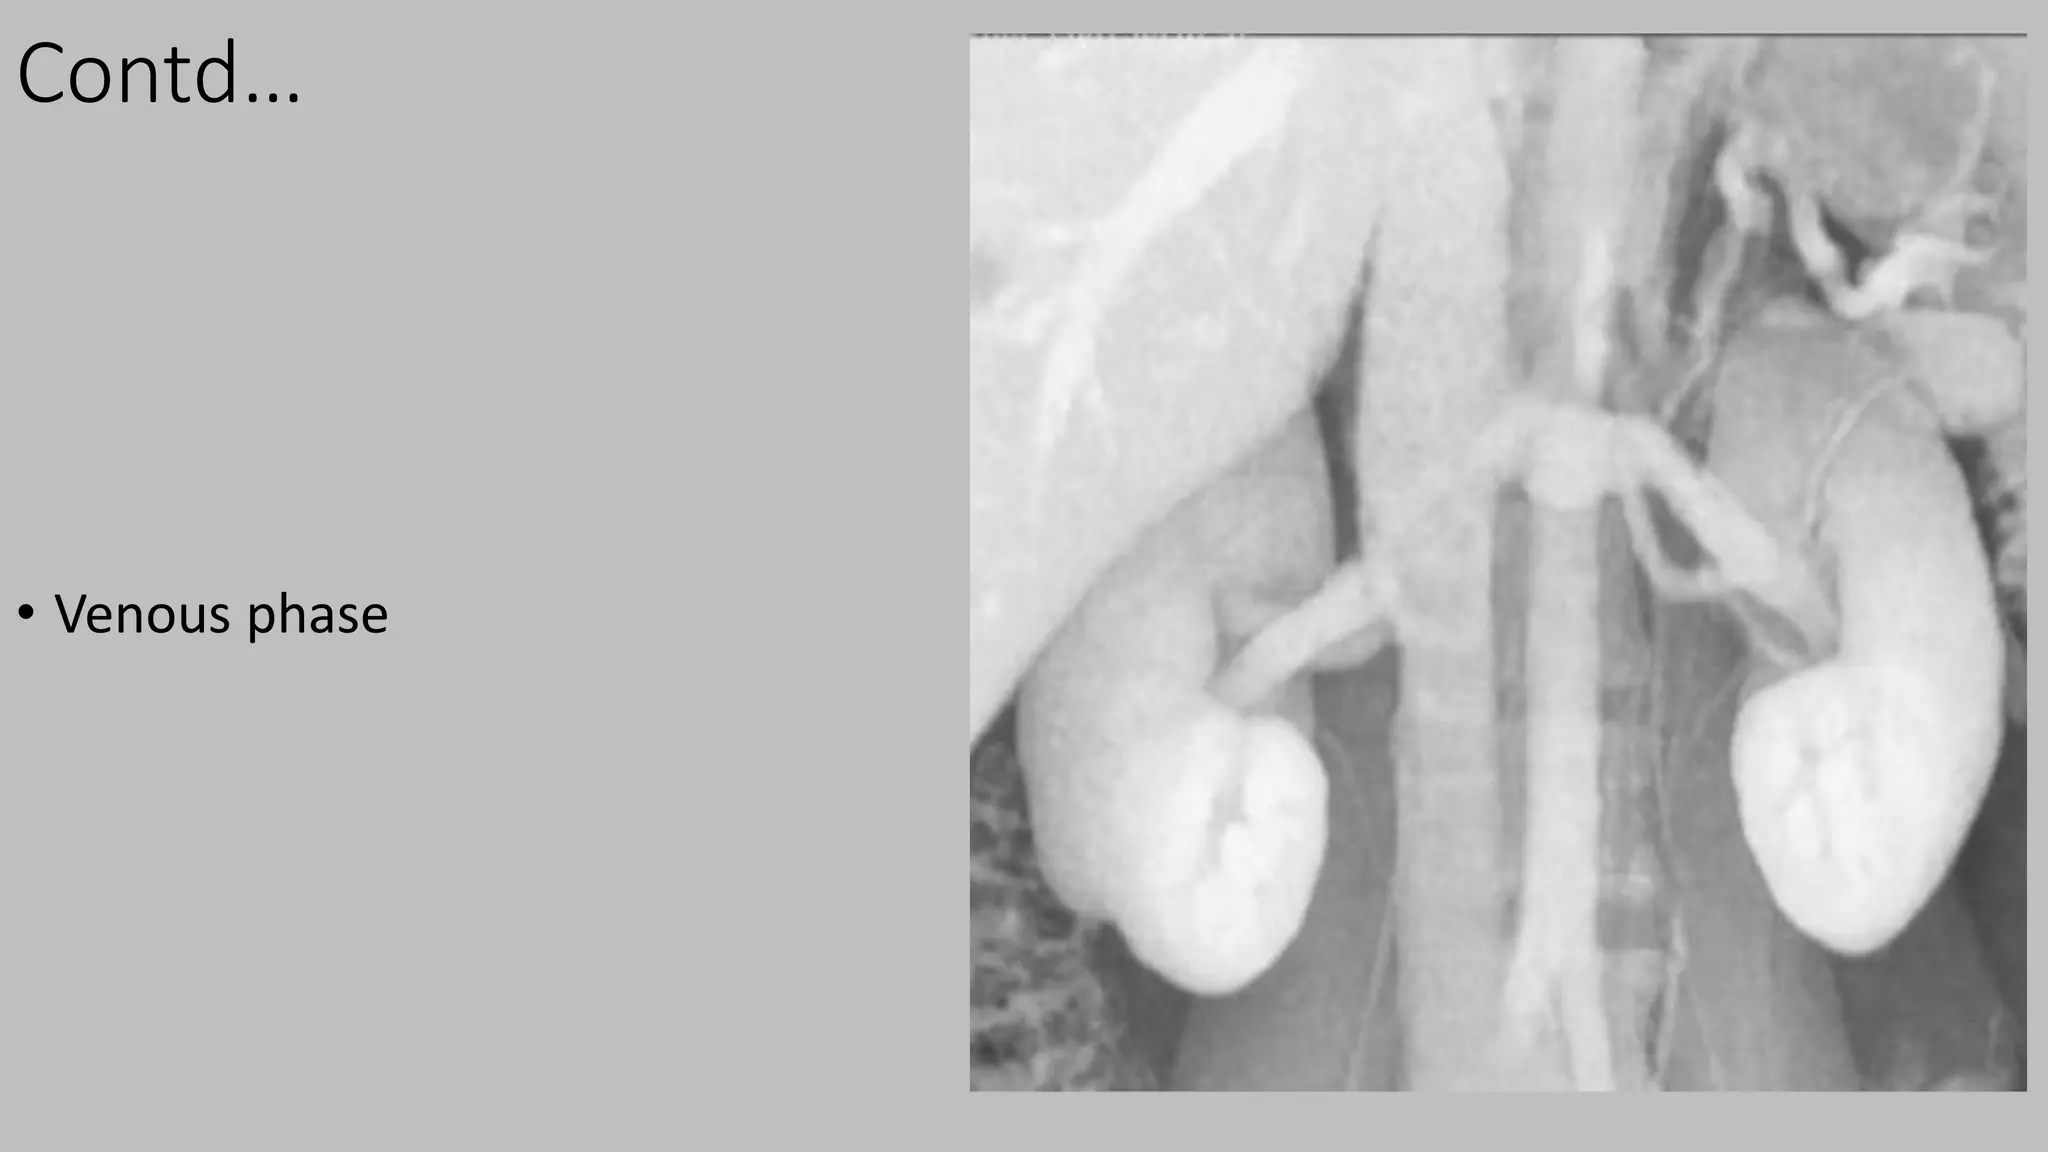

Contd…

• Venous phase